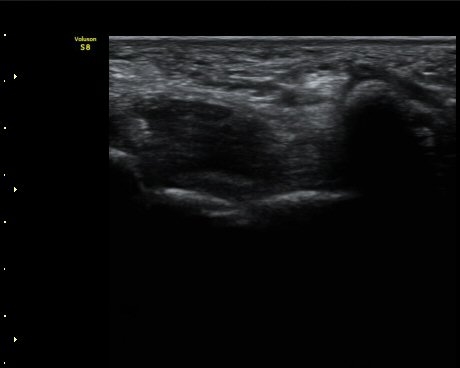

ŽÃËÀÚ¸¦ Á¶±Ý ´õ ¸»´ÜÀ¸·Î À̵¿ÇÏ´Ï Ã´°ñ½Å°æ ½ÉºÎ¿îµ¿°¡ÁöÀÇ ºÎÁ¾ÀÌ °üÂûµÇ°í ½Å°æ ¿äÃøÀ¸·Î Àú¿¡ÄÚ

¿øÇüÀÇ Á¾±«°¡ °üÂûµÈ´Ù(»çÁø 4, 5).

ŽÃËÀÚ¸¦ Á¾±«ÀÇ Á¾´Ü¸éÀ¸·Î À§Ä¡ÇÏ´Ï ÀÌÁúÀûÀÎ ¿¡ÄÚ¸¦ º¸À̴ Ÿ¿øÇüÀÇ Á¾±«°ú °üÂûµÇ°í

Á¾±« Ç¥ÃþÀ¸·Î Á¤Áß½Å°æ °¡Áö°¡ °üÂûµÈ´Ù.

ô°ñ½Å°æ ½ÉºÎ¿îµ¿°¡Áö´Â Á¾±«ÀÇ ½ÉÃþ¿¡ À§Ä¡ÇÒ °ÍÀ¸·Î ÆÇ´ÜµÇ´Âµ¥ ±¸ºÐµÇÁö ¾Ê´Â´Ù(»çÁø 6).